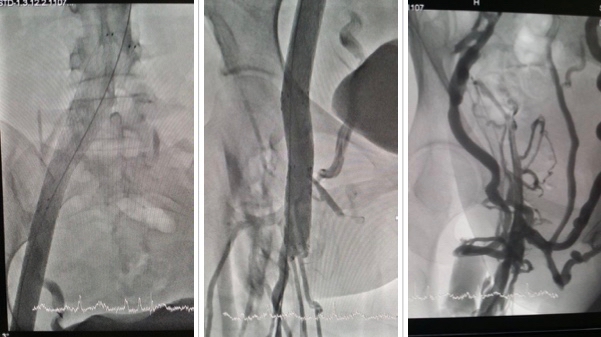

Prise en charge du syndrome post-thrombotique